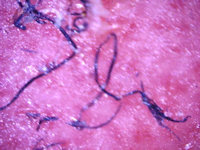

![Morgellons disease: pluisjes op de huid (en jeuk) (click on photo to enlarge) [source: Marianne J Middelveen - Wikimedia - Creative Commons License 4.0] Morgellons disease: pluisjes op de huid (en jeuk)](../../../images/morgellons-disease-1z.jpg) |

![Morgellons disease: pluisjes op de huid (en jeuk) (click on photo to enlarge) [source: www.huidziekten.nl] Morgellons disease: pluisjes op de huid (en jeuk)](../../../images/morgellons-disease-2z.jpg) |

| Morgellons

disease |

Morgellons

![Morgellons disease: pluisjes op de huid (en jeuk) (click on photo to enlarge) [source: Marianne J Middelveen - Wikimedia - Creative Commons License 4.0] Morgellons disease: pluisjes op de huid (en jeuk)](../../../images/morgellons-disease-3z.jpg) |

![Morgellons disease: pluisjes op de huid (en jeuk) (click on photo to enlarge) [source: Marianne J Middelveen - Wikimedia - Creative Commons License 4.0] Morgellons disease: pluisjes op de huid (en jeuk)](../../../images/morgellons-disease-4z.jpg) |

Foto's: Marianne J Middelveen et al. Wikimedia (Creative Commons

License

4.0).